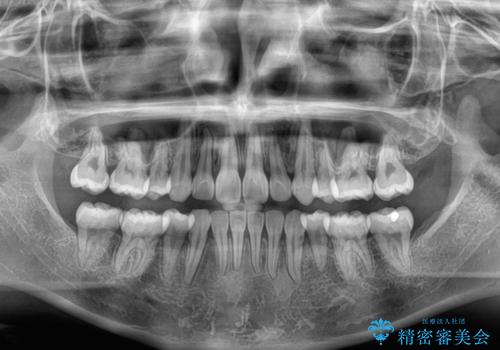

- 口を閉じたときに飛び出してしまう上顎前歯を気にして来院された患者様です。

下顎はデコボコが気になっていたため、上下左右第一小臼歯4本を抜去して、ワイヤー装置にて口元の突出感を改善するよう矯正治療を行うこととしました。